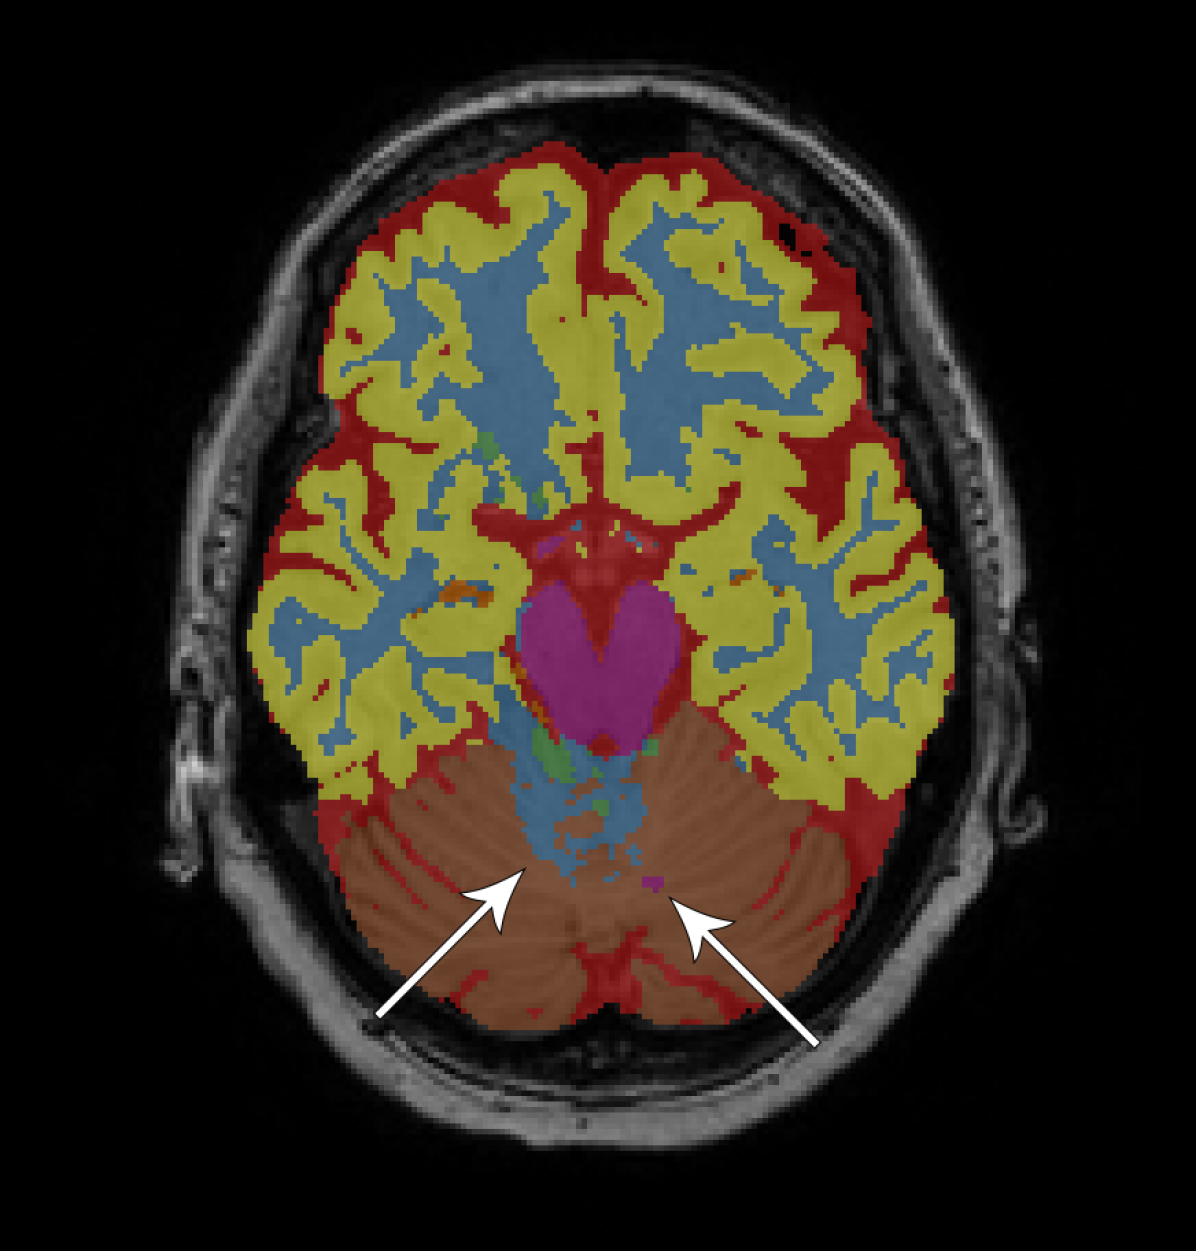

Figure 2 provides a visual comparison between the segmentations obtained with and without adversarial training, showing that the adversarial approach generally resulted in less noisy segmentations. The same can be seen from the total number of 3D components (including the background class) that compose the segmentations. For the adult subjects, the number of components per image () decreased from to using the fully convolutional network and from to using the dilated network. For the elderly subjects, the number of components per image () decreased from to using the fully convolutional network and from to using the dilated network.

We have presented an approach to improve brain MRI segmentation by adversarial training. The results showed improved segmentation performance both qualitatively (Figure 2) and quantitatively in terms of DC (Figure 3). The improvements were especially clear for the deeper, more difficult to train, fully convolutional networks as compared with the more shallow dilated networks. Furthermore, the approach improved structural consistency, e.g. visible from the reduced number of components in the segmentations. Because these improvements were usually small in size, their effect on the DC was limited.